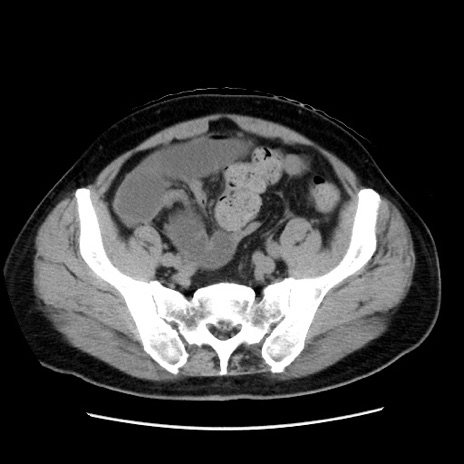

症例16(横断像)

【症例】 70歳代男性

【主訴】 腹痛、嘔吐

【現病歴】 約1ヶ月前より間欠的に腹痛と嘔吐あり、当院消化器内科を受診したところCTで多発する肝臓のLDAを指摘され、精査中であった。以降は消化器症状は安定していたが、2日前より嘔気と腹痛があり、同日より排便・排ガスが消失した。改善認めず、 本日、救急外来を受診した。

【既往歴】 大腸ポリープ切除後。

【身体所見】意識清明・会話良好、BT 36.3℃、BP 127/80mmHg、 P 80bpm、腹部:膨満あり、平坦・軟、上腹部正中および下腹部正中に圧痛あり、反跳痛なし、筋性防御なし。

【データ】WBC 7200、CRP 0.77